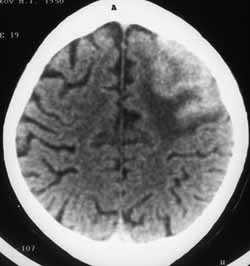

Рис. 11. Туберкулома левого полушария головного мозга. По своим характеристикам напоминает геморрагический ушиб.